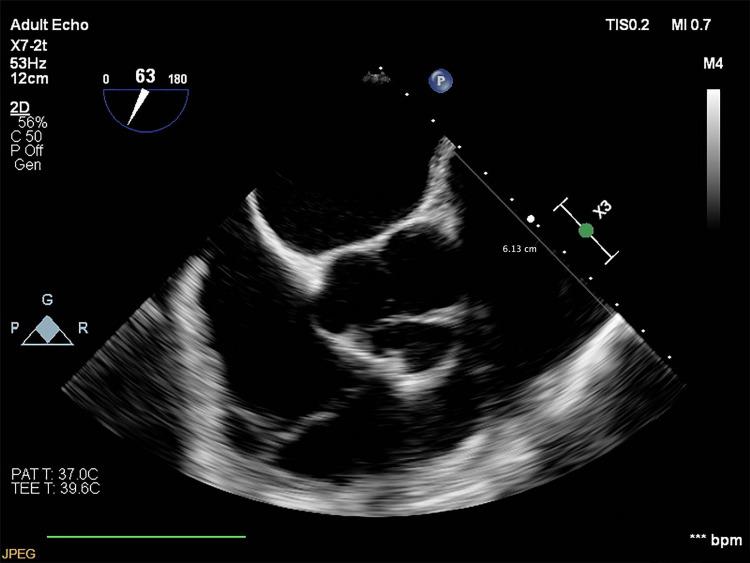

A Novel Approach for the Treatment of Pulmonary Artery Aneurysm Repair Using Inclusion Technique: A Case Report.

Right ventricle outflow tract dilatation and pulmonary artery aneurysm, rare cardiac conditions.

Symptomatic idiopathic pulmonary artery aneurysm: a case report and a mini-review of the literature.

Management of Giant Pulmonary Artery Aneurysm with Quadricuspid Valve Stenosis.

Improvement of lung function and pulmonary hypertension after pulmonary aneurysm repair: case series.

A Case of Preoperative Diagnosis of Pulmonary Artery Aneurysm Resected by Segmentectomy.

David's procedure for pulmonary artery aneurysm.